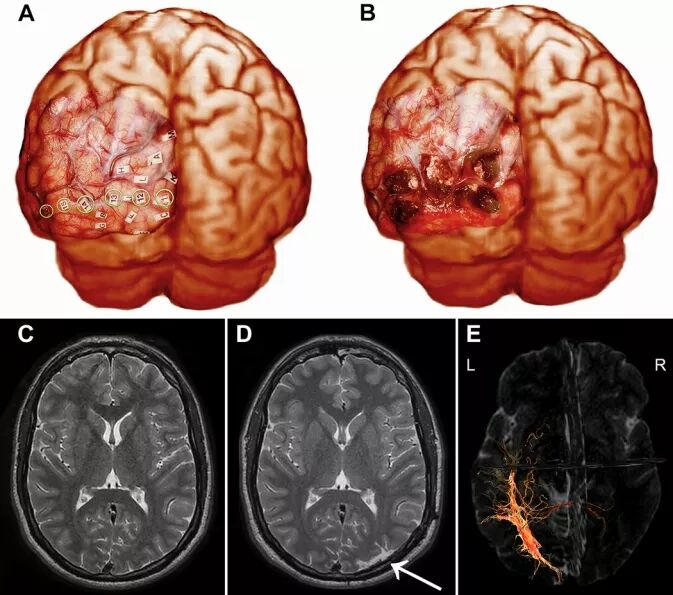

作者列举1例枕叶癫痫患者的诊治过程,说明手术中唤醒麻醉技术的应用效果。患者男性,26岁,右利手,枕叶癫痫病史10年。自诉视物变形,右侧视力模糊,偶发意识丧失和自动症等症状。神经系统检查,包括视野检查,结果均正常。头皮脑电图(electroencephalography,EEG)提示T5枕部有大量痫样放电,并迅速扩散至同侧颞叶。颅脑MRI检查无异常。为了识别痫灶发作区(seizure onset zone,SOZ),于左颞叶、顶叶和枕叶进行硬膜下电极植入,记录生理电活动。最终,于左枕叶精确地确定痫灶位置在电极111-114,早期痫样放电播散至电极115和116(图1A)。根据临床症状和侵入性脑电图检查记录,推测癫痫发作可能起源于左侧视觉相关区域,而非初级视觉皮质。硬膜下电极电刺激结果表明,SOZ位于初级视觉皮质外。由于SOZ与初级视觉皮质接近及患者视野检查为正常,作者决定在唤醒麻醉下进行皮质电刺激监测,给予最大程度地安全切除致痫灶(图1)。

硬膜下电极刺激后6个月进行致痫灶切除手术。使用StealthStation神经导航软件将患者的颅脑CT图像与手术当天的MRI图像融合。患者取右侧卧位,用1%利多卡因或0.5%布比卡因和肾上腺素(1:200,000)混合液作头皮局部阻滞麻醉后,头部固定在3钉架上。施行静脉异丙酚/瑞芬太尼的镇静-唤醒-镇静麻醉,做“马蹄形”皮瓣切口开颅,暴露枕叶。在患者完全清醒下,用单极电刺激枕叶皮质。嘱患者在前方的视野监测板上,描绘术中视野图。当视觉皮质区接受持续电刺激时,患者用激光笔在视野监测板上描出感应方位,以确认视力的全部正向或负向变化。在监测板上标记字母,以表示相应的皮质区域(图1A、图2)。刺激初级视觉皮质区时,患者眼前出现简单的黑白光扭曲图像,刺激视觉相关皮质区时则出现变形的物体图像。由于初级视觉皮质与触点11和12重叠,故仅切除与触点13至16对应的皮质(图1B)。在软膜下行皮质切除,保留皮质血管以及白质。

图1. A.暴露左侧枕叶皮质后,用3.5mA单极电刺激视觉皮质;B.皮质切除术后图像;C.术前MRI成像;D.术后MRI成像显示左枕皮质的切除范围(箭头);E.术前MRI弥散张量成像显示左侧视神经纤维束成像。